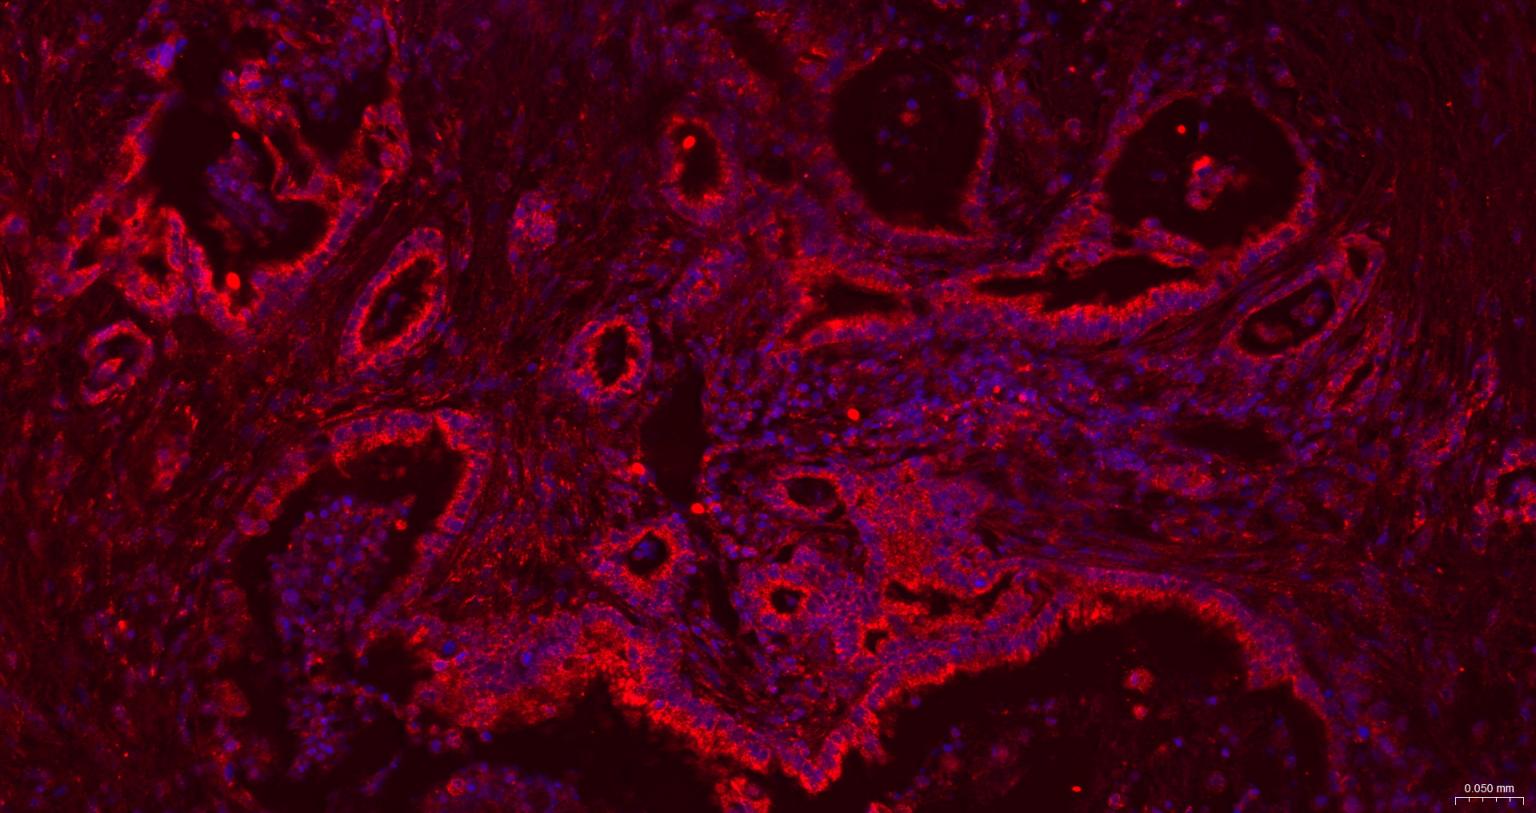

| IF | Human, Mouse, Rat | Rabbit, Pig, Cow, Dog, Horse | 1:100-500 |